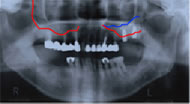

当院のインプラント治療では3次元CTを用いて、まず患者さまのあごの骨を徹底的に解析します。

そして骨の構造を分析した上で、成功率の高い2回法によるインプラント治療をおこないます。

治療例